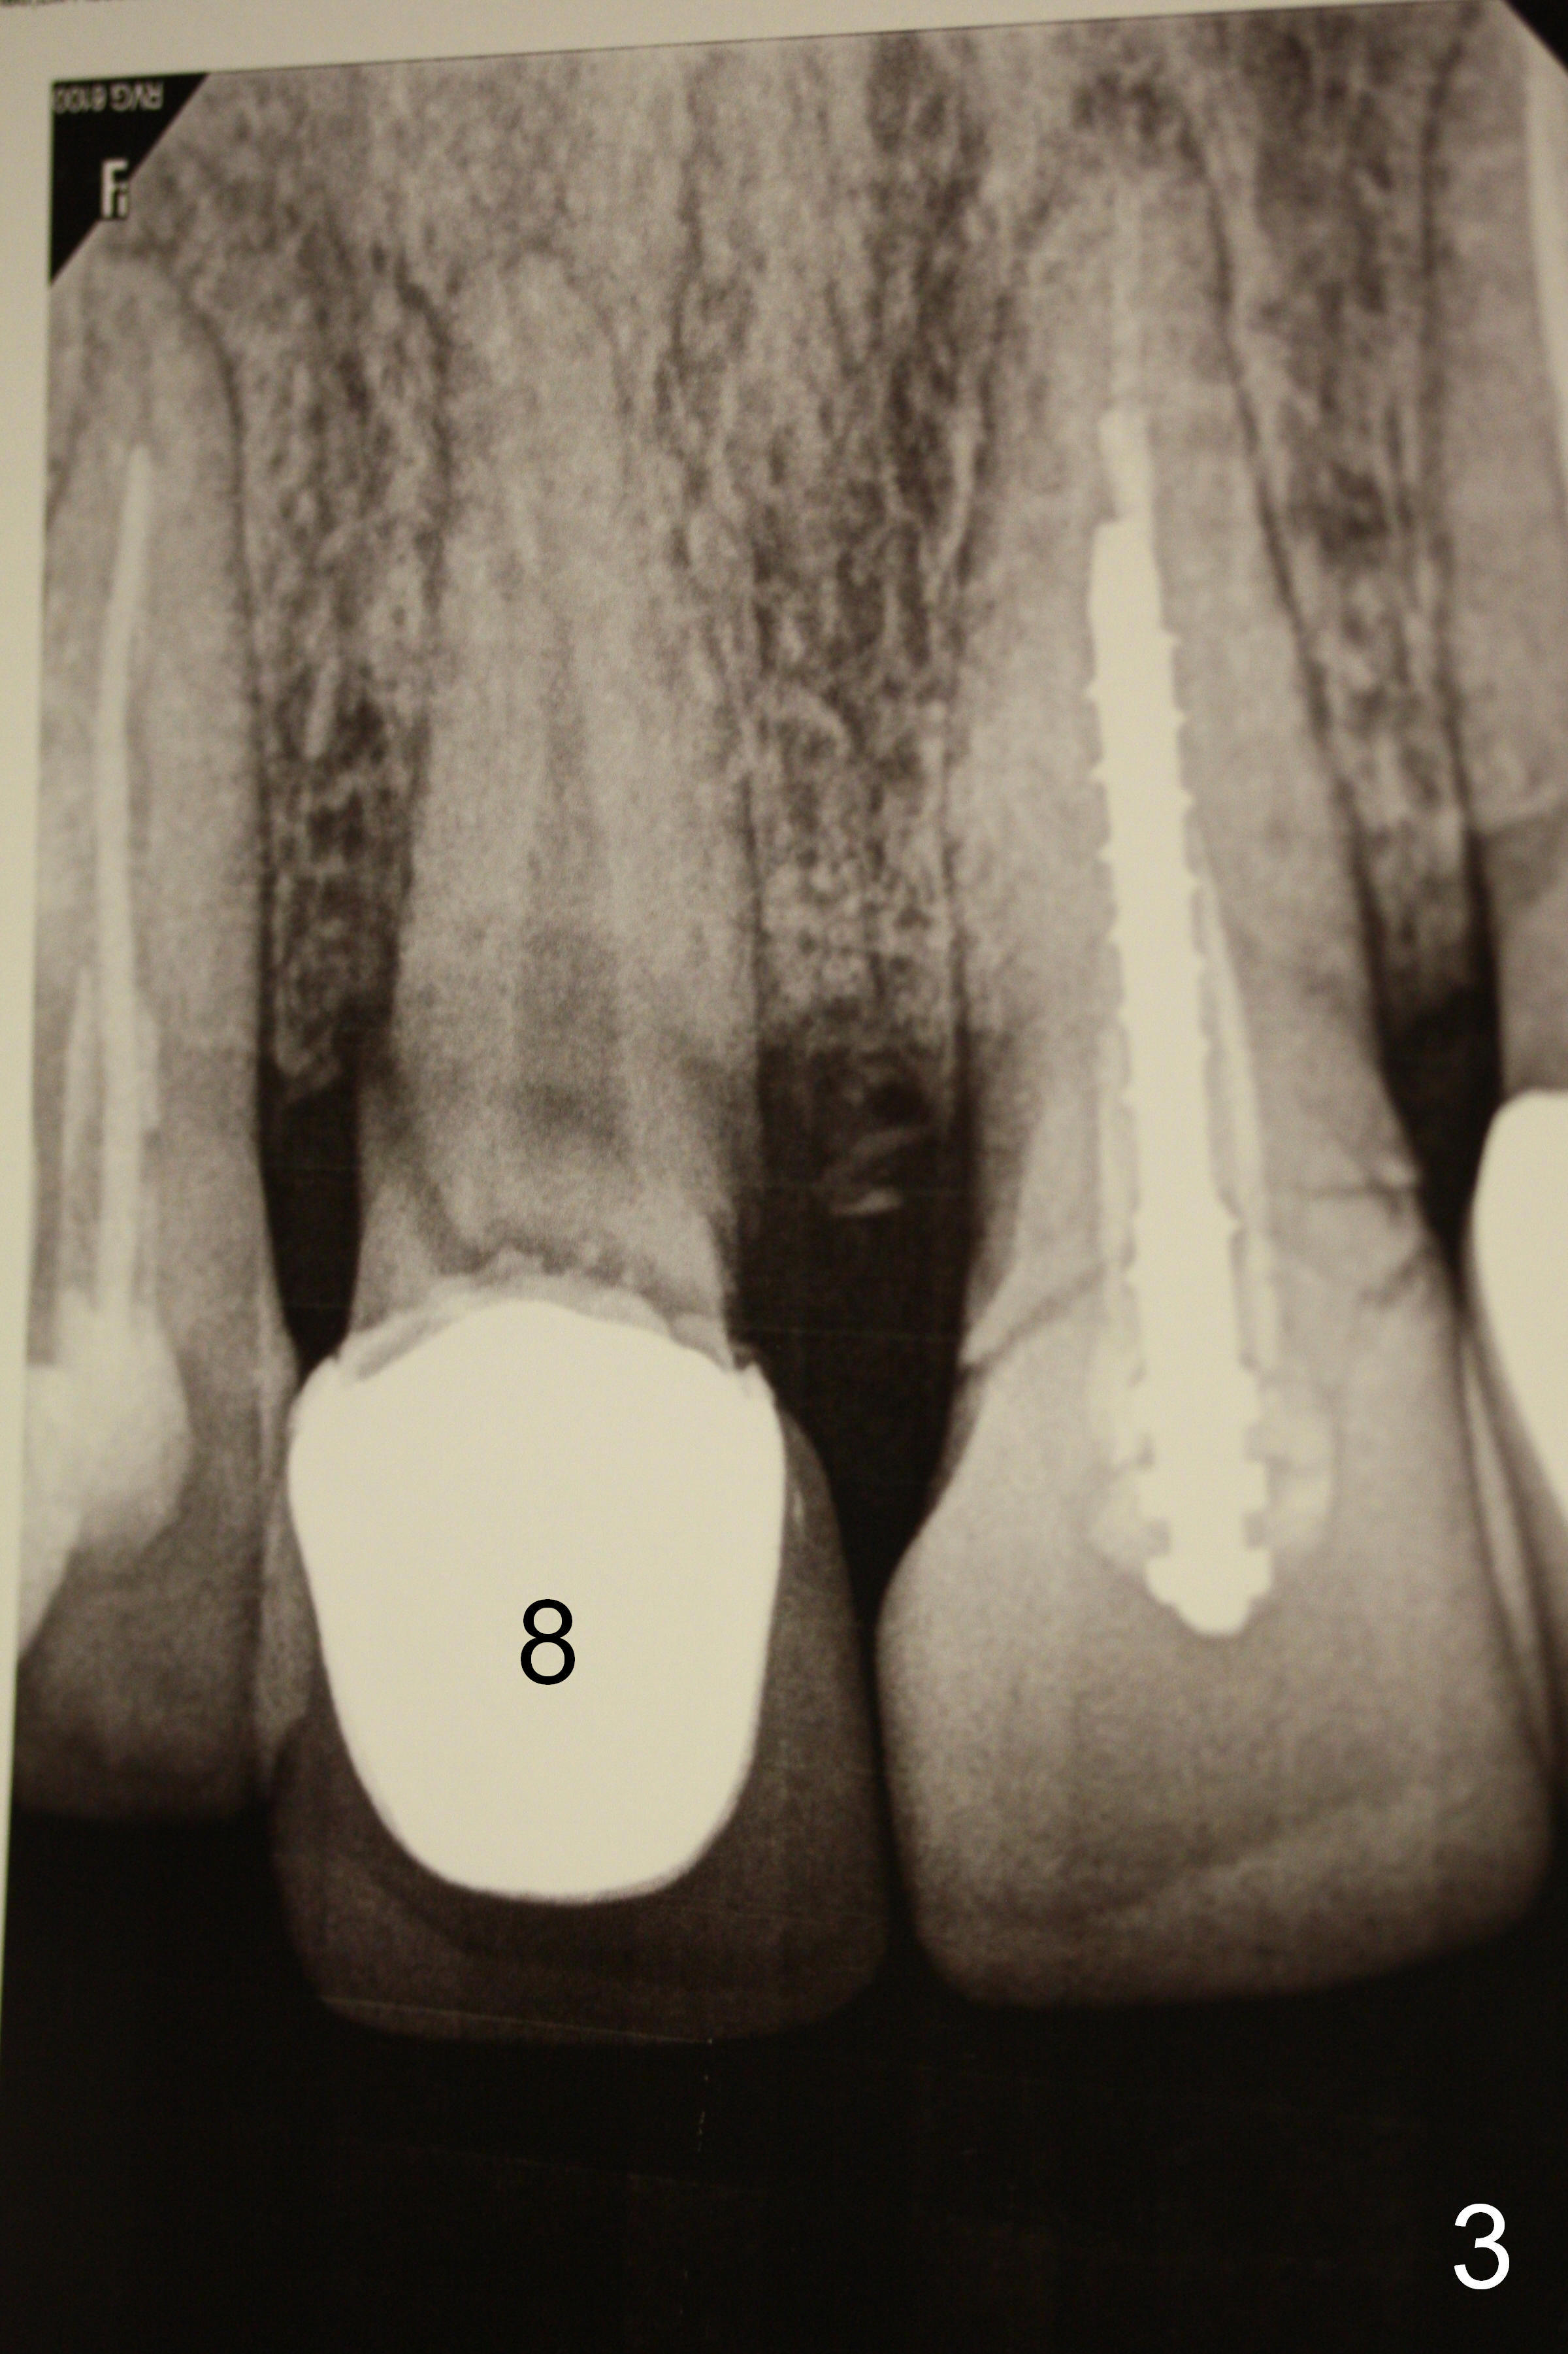

A 40-year-old lady has multiple restorations (Fig.1). Two of them require implants (#4 (Fig.2, severe caries) and #8 (Fig.3, root fracture).  The root of #4 is long and curved (Fig.2).  It may present a challenge to extraction, but not implant placement.  The narrow and long root is favorable to primary stability.  A 2 mm pilot drill is used to initiate osteotomy in the palatal wall of the socket, followed by 2.5 and 3 mm reamers at 17 mm (gingival level).  If the bone is soft, the depth for the 3 mm reamer will be reduced to 14 mm.  A 4.5x20 mm Tatum tapered tap will be used at 17 mm deep to test stability.